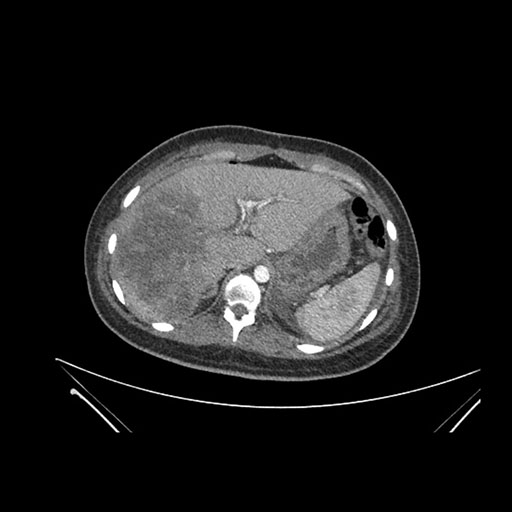

Imaging Analysis

Look through the patient's CT scan to identify any areas of concern for the necessary procedure.

Axial Arterial

Based on initial findings, which issue(s) would you be most concerned about?